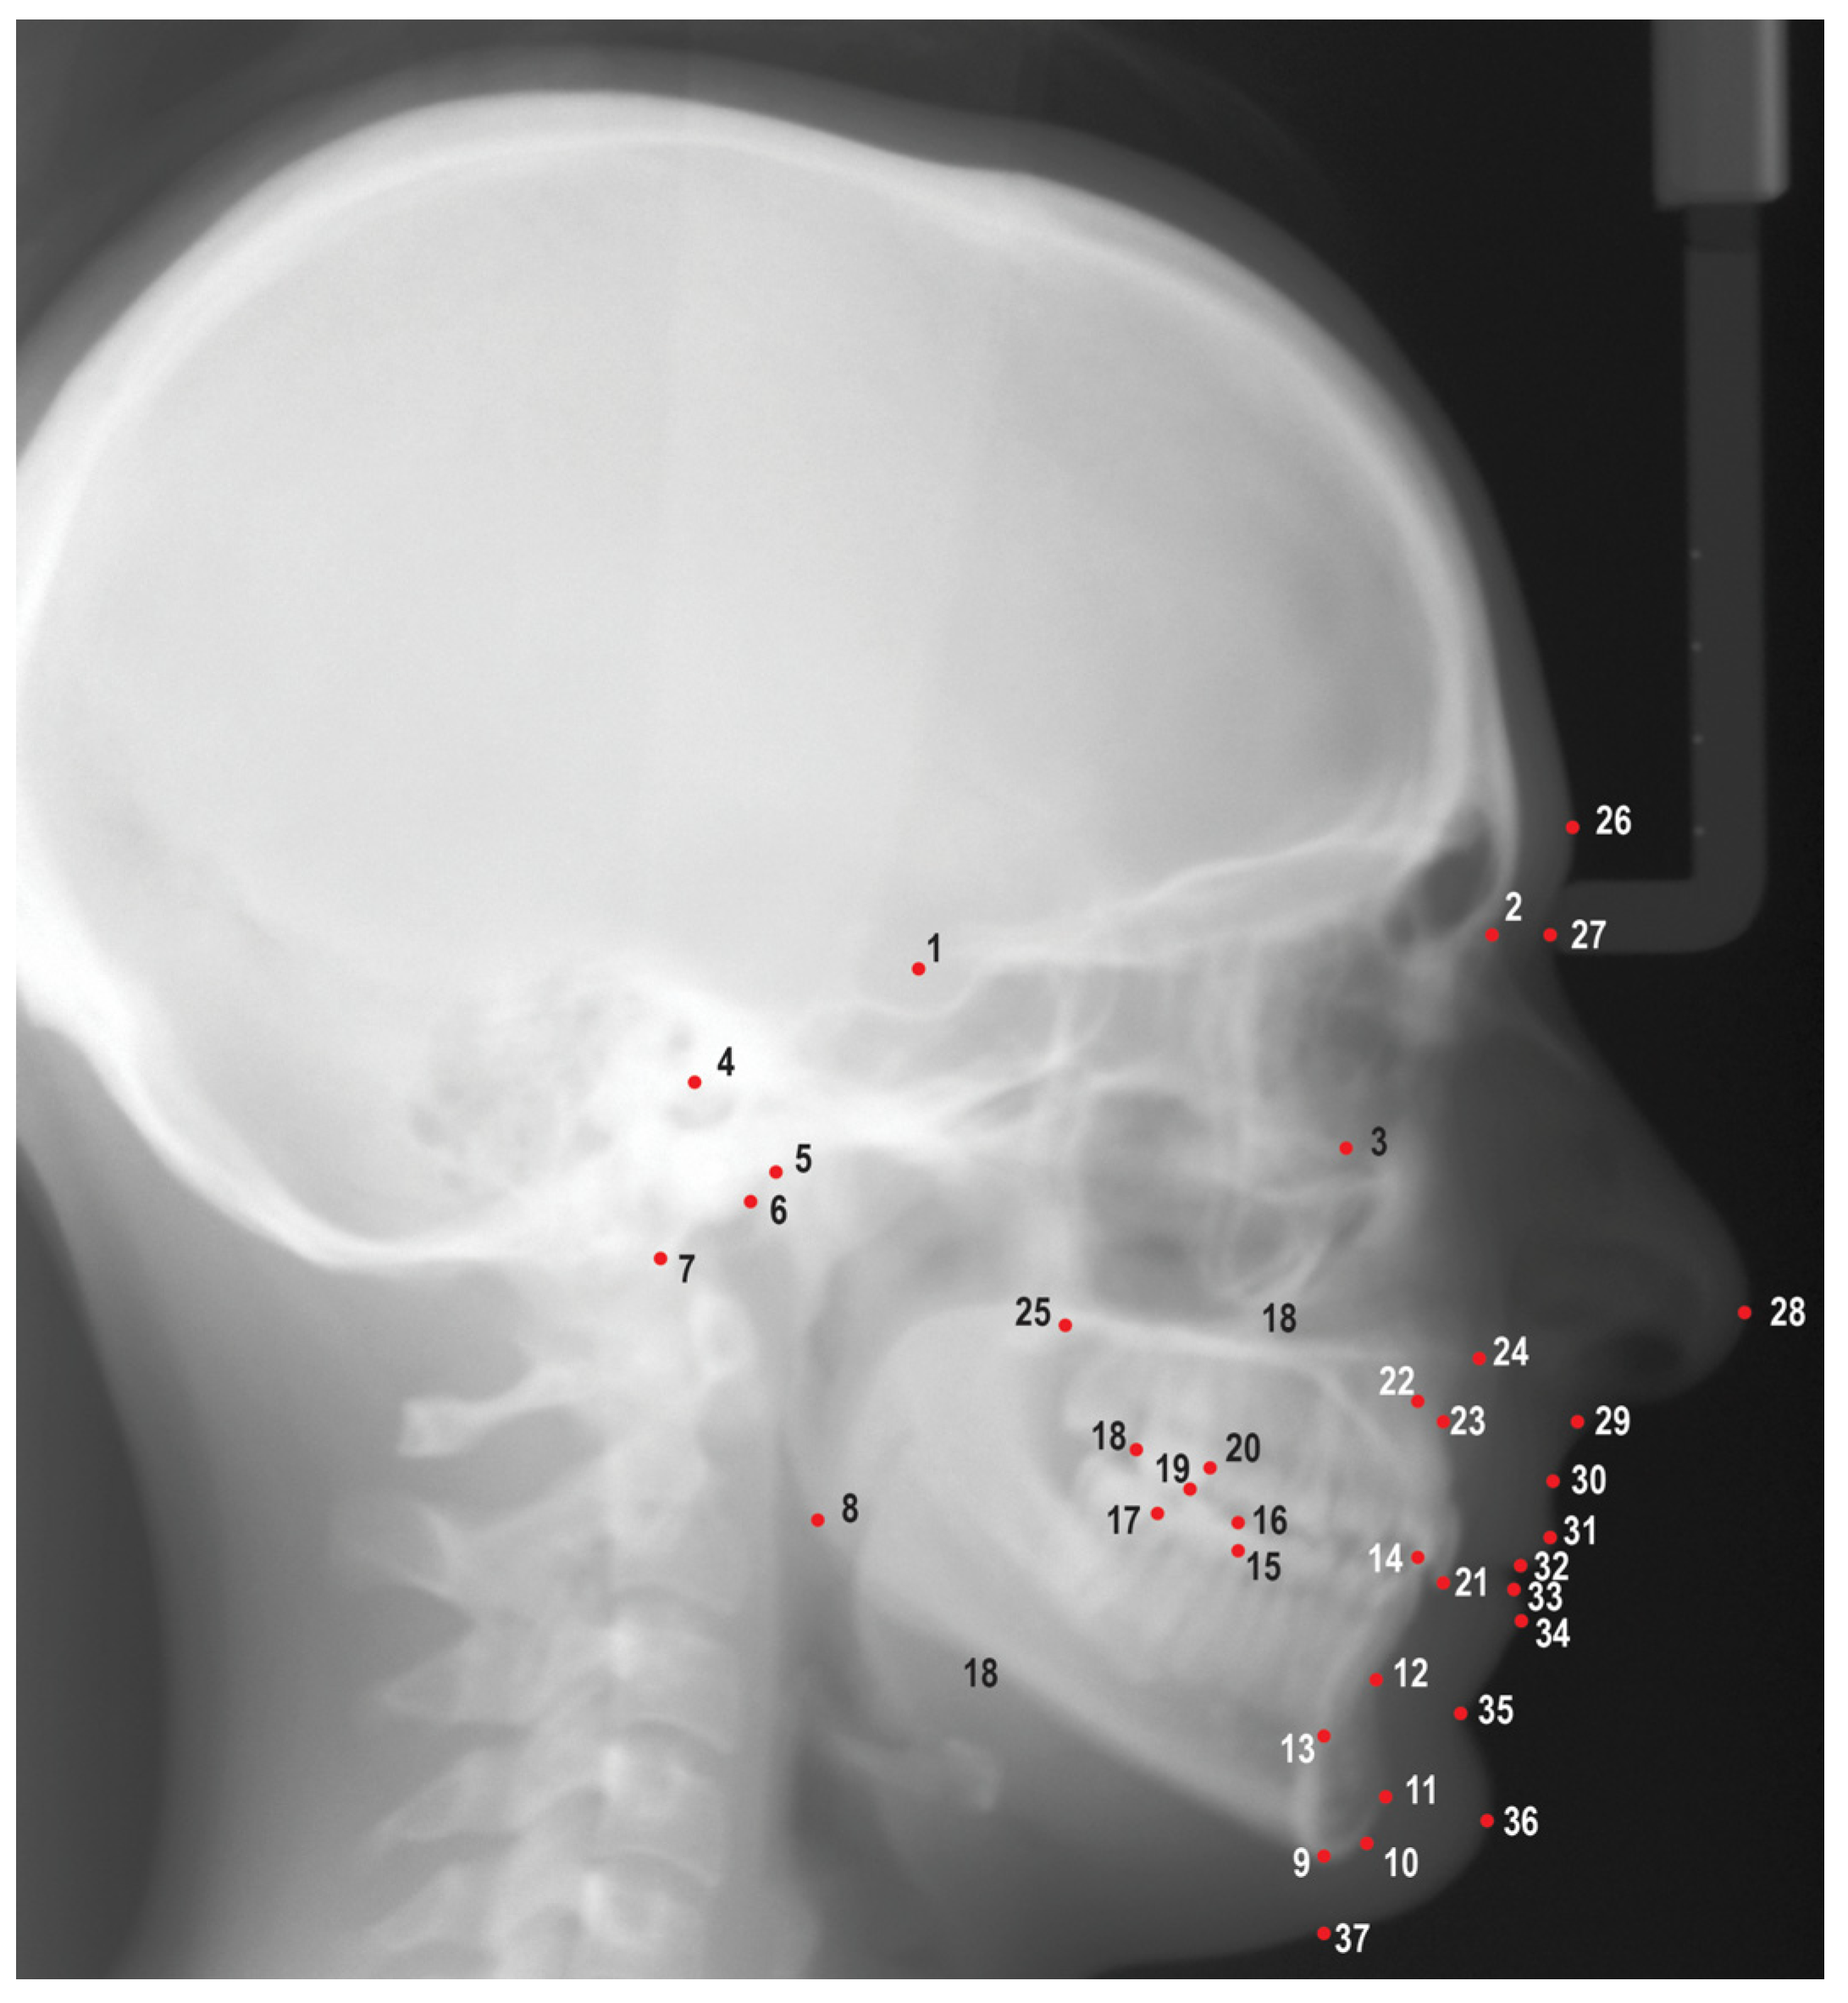

Digital images from the AAOF repository were uploaded into Dolphin Imaging v. 11.95 (Dolphin Imaging and Management Solutions, Chatsworth, Calif, USA) and were traced by a single investigator (M.P.) using 25 hard tissue landmarks and 12 soft tissue landmarks (

Figure 1). A total of 47 linear and angular measurements were measured and recorded; definitions of the measurements are listed in

Figure 1.

Cephalometric landmarks used in this study. 1. Sella (S), 2. Nasion (N), 3. Orbitale (Or), 4. Porion (Po), 5. Condylion (Co), 6. Articulare (Ar), 7. Basion (Ba), 8. Gonion (Go), 9. Menton (Me), 10. Gnathion (Gn), 11. Pogonion (Pog), 12. B point (B), 13. Lower incisor root apex (L1a), 14. Lower incisor incisal edge (L1i), 15. Mesial of lower first molar (L6m), 16. Mesiobuccal cusp of lower first molar (L6mb), 17. Distal of lower first molar (L6d), 18. Distal of upper first molar (U6d), 19. Mesiobuccal cusp of upper first molar (U6mb), 20. Mesial of upper first molar (U6m), 21. Upper incisor incisal edge (U1i), 22. Upper incisor root apex (U1a), 23. A point (A), 24. Anterior nasal spine (ANS), 25. Posterior nasal spine (PNS), 26. Glabella (G), 27. Soft tissue nasion (N'), 28. Pronasale (Pn), 29. Subnasale (Sn), 30. Soft tissue A point (A’), 31. Upper lip (Ls), 32. Stomion superioris (Ss), 33. Stomion inferioris (Si), 34. Lower lip (Li), 35. Soft tissue B point (B’), 36. Soft tissue pogonion (Pog'), 37. Soft tissue menton (Me').